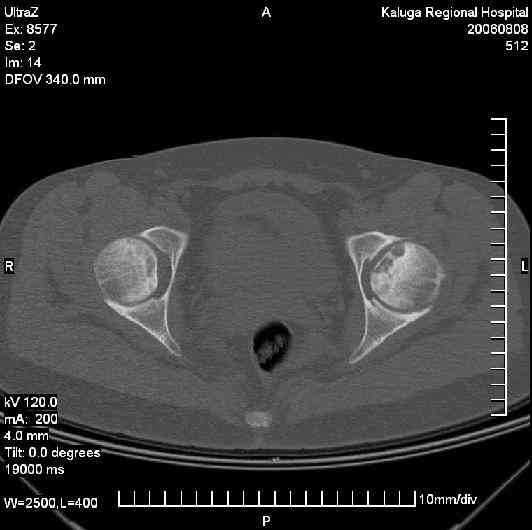

Уважаемые коллеги! Подскажите как быть? Моя родственница и одновременно пациентка(30 лет) выполнила по поводу болей в тазобедренном суставе КТ.

Боли по нарастающей беспокоили в течении 2 лет. Клинически имеет место прихрамывание и незначительное ограничение отведения.Подход к проблеме в детстве приблизительно ясен. Как быть в данном случае?Процесс развивается и на контрлатеральной стороне.Фото прилагается.

Поскольку Вы говорите,что развивается процесс контролатеральной стороны, на КТ я пока не вижу какихто серьезных изменений, а рентгенограмм нет,могу поделиться единичным собственным опытом.

В данной ситуации самый оптимальный выход - эндопротезирование тазобедренного сустава. Даже на представленой кт-грамме имееются признаки перелома субхондральной костной пластины в области зоны некроза. Думаю на стандартной рентгенограмме и кт-срезах максимально нагружаемых зон головки картина была бы более показательной. На данной стадии заболевания любые так называемые "органно-сохраняющие" операции малоэффективны. Любая хирургическая агрессия приведет лишь к ухудшению кровообращения головки бедра,а ротационно-флексионная остеотомия - к нарушению биомиханики сустава (с последующим быстрым развитием вторичного артроза).Как следствие - дальнейшее быстрое разрушение головки бедра. Кроме того, послеоперационный период после данных операций очень обременитеный для больных (безнагрузочный период оперированной конечности до 3 месяцев, период полной реабилитации до 6 месяцев). Эффект от таких операций, по нашему опыту, не более 5 лет (как правило около 3 лет), затем снова встанет вопрос о необходимости эндопротезирования. Правильно подобранный и установленый имплантат (эндопротез)дает пациенту 15-20 лет нормальной, в бытовом плане полностью адаптированной жизни. В последующем потребуется ревизионное эндопротезирование. На мой взгляд стоит принять совет господина Мамонова о необходимости дальнейшего обследования пациета на предмет выявления причин развития асептичекого некроза. На исход леченич пораженных головок бедренных костей это не повлияет, но вовремя начатое лечение, возможно,поможет избежать поражению других костей (плечевая, таранная, ладьевидная и т.п.).